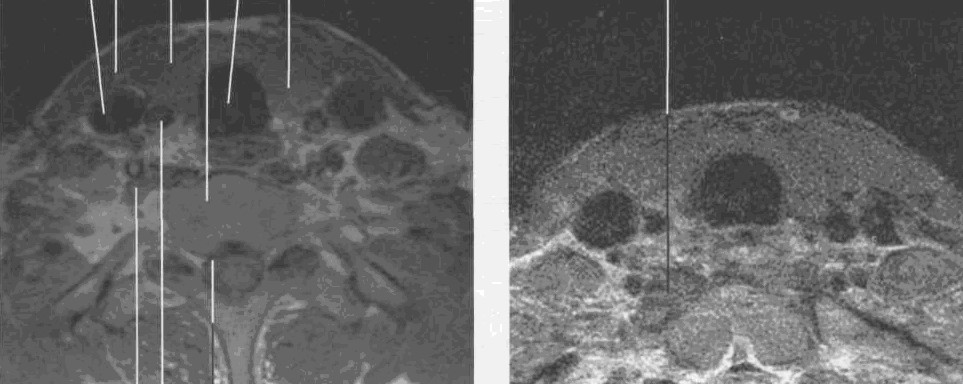

Магнитно-резонансная томография ЩЖ

На МРТ щитовидная железа имеет значительно более интенсивный сигнал, чем грудино-щитовидная мышца на Т2-ВИ.

Сонная артерия и яремная вена располагаются латерально от щитовидной железы и имеют низкую интенсивность.

Щитовидная железа имеет клиновидную форму, располагается по сторонам от трахеи, сим­метричная, однородной структуры.

Перешеек железы перекрывает спереди второе и третье трахеальные кольца и соединяет ниж­ние отделы правой и левой долей.

Капсула железы фиксируется к претрахеальной фасции, что дает ей возможность двигаться вместе с глоткой.

Проведения МРТ-исследования в аксиальном изображении часто достаточно для исследо­вания щитовидной железы. Когда требуется уточнить краниокаудальные контуры и размеры же­лезы, фронтальная  плоскость среза предпочтительнее, так как симметричность ее лучше оценивает­ся в этой плоскости.

Нормальная щитовидная железа легко дифференцируется от грудины и грудино-ключично-сосцевидной мышцы, так как увеличенное время Т2 релаксации приводит к усилению сигнала интенсивности на Т2-ВИ.

Паращитовидные железы в норме не видны ни на ультразвуковых, ни на КТ-, ни на МРТ-изображениях (рис. 29,30).

Рис. 29. MPT щитовидной железы

в аксиальной плоскости на уровне щитовидного хряща. Т1-ВИ

Рис. 30. МРТ щитовидной железы в аксиальной плоскости  на уровне щитовидного хряща. Т2-ВИ.